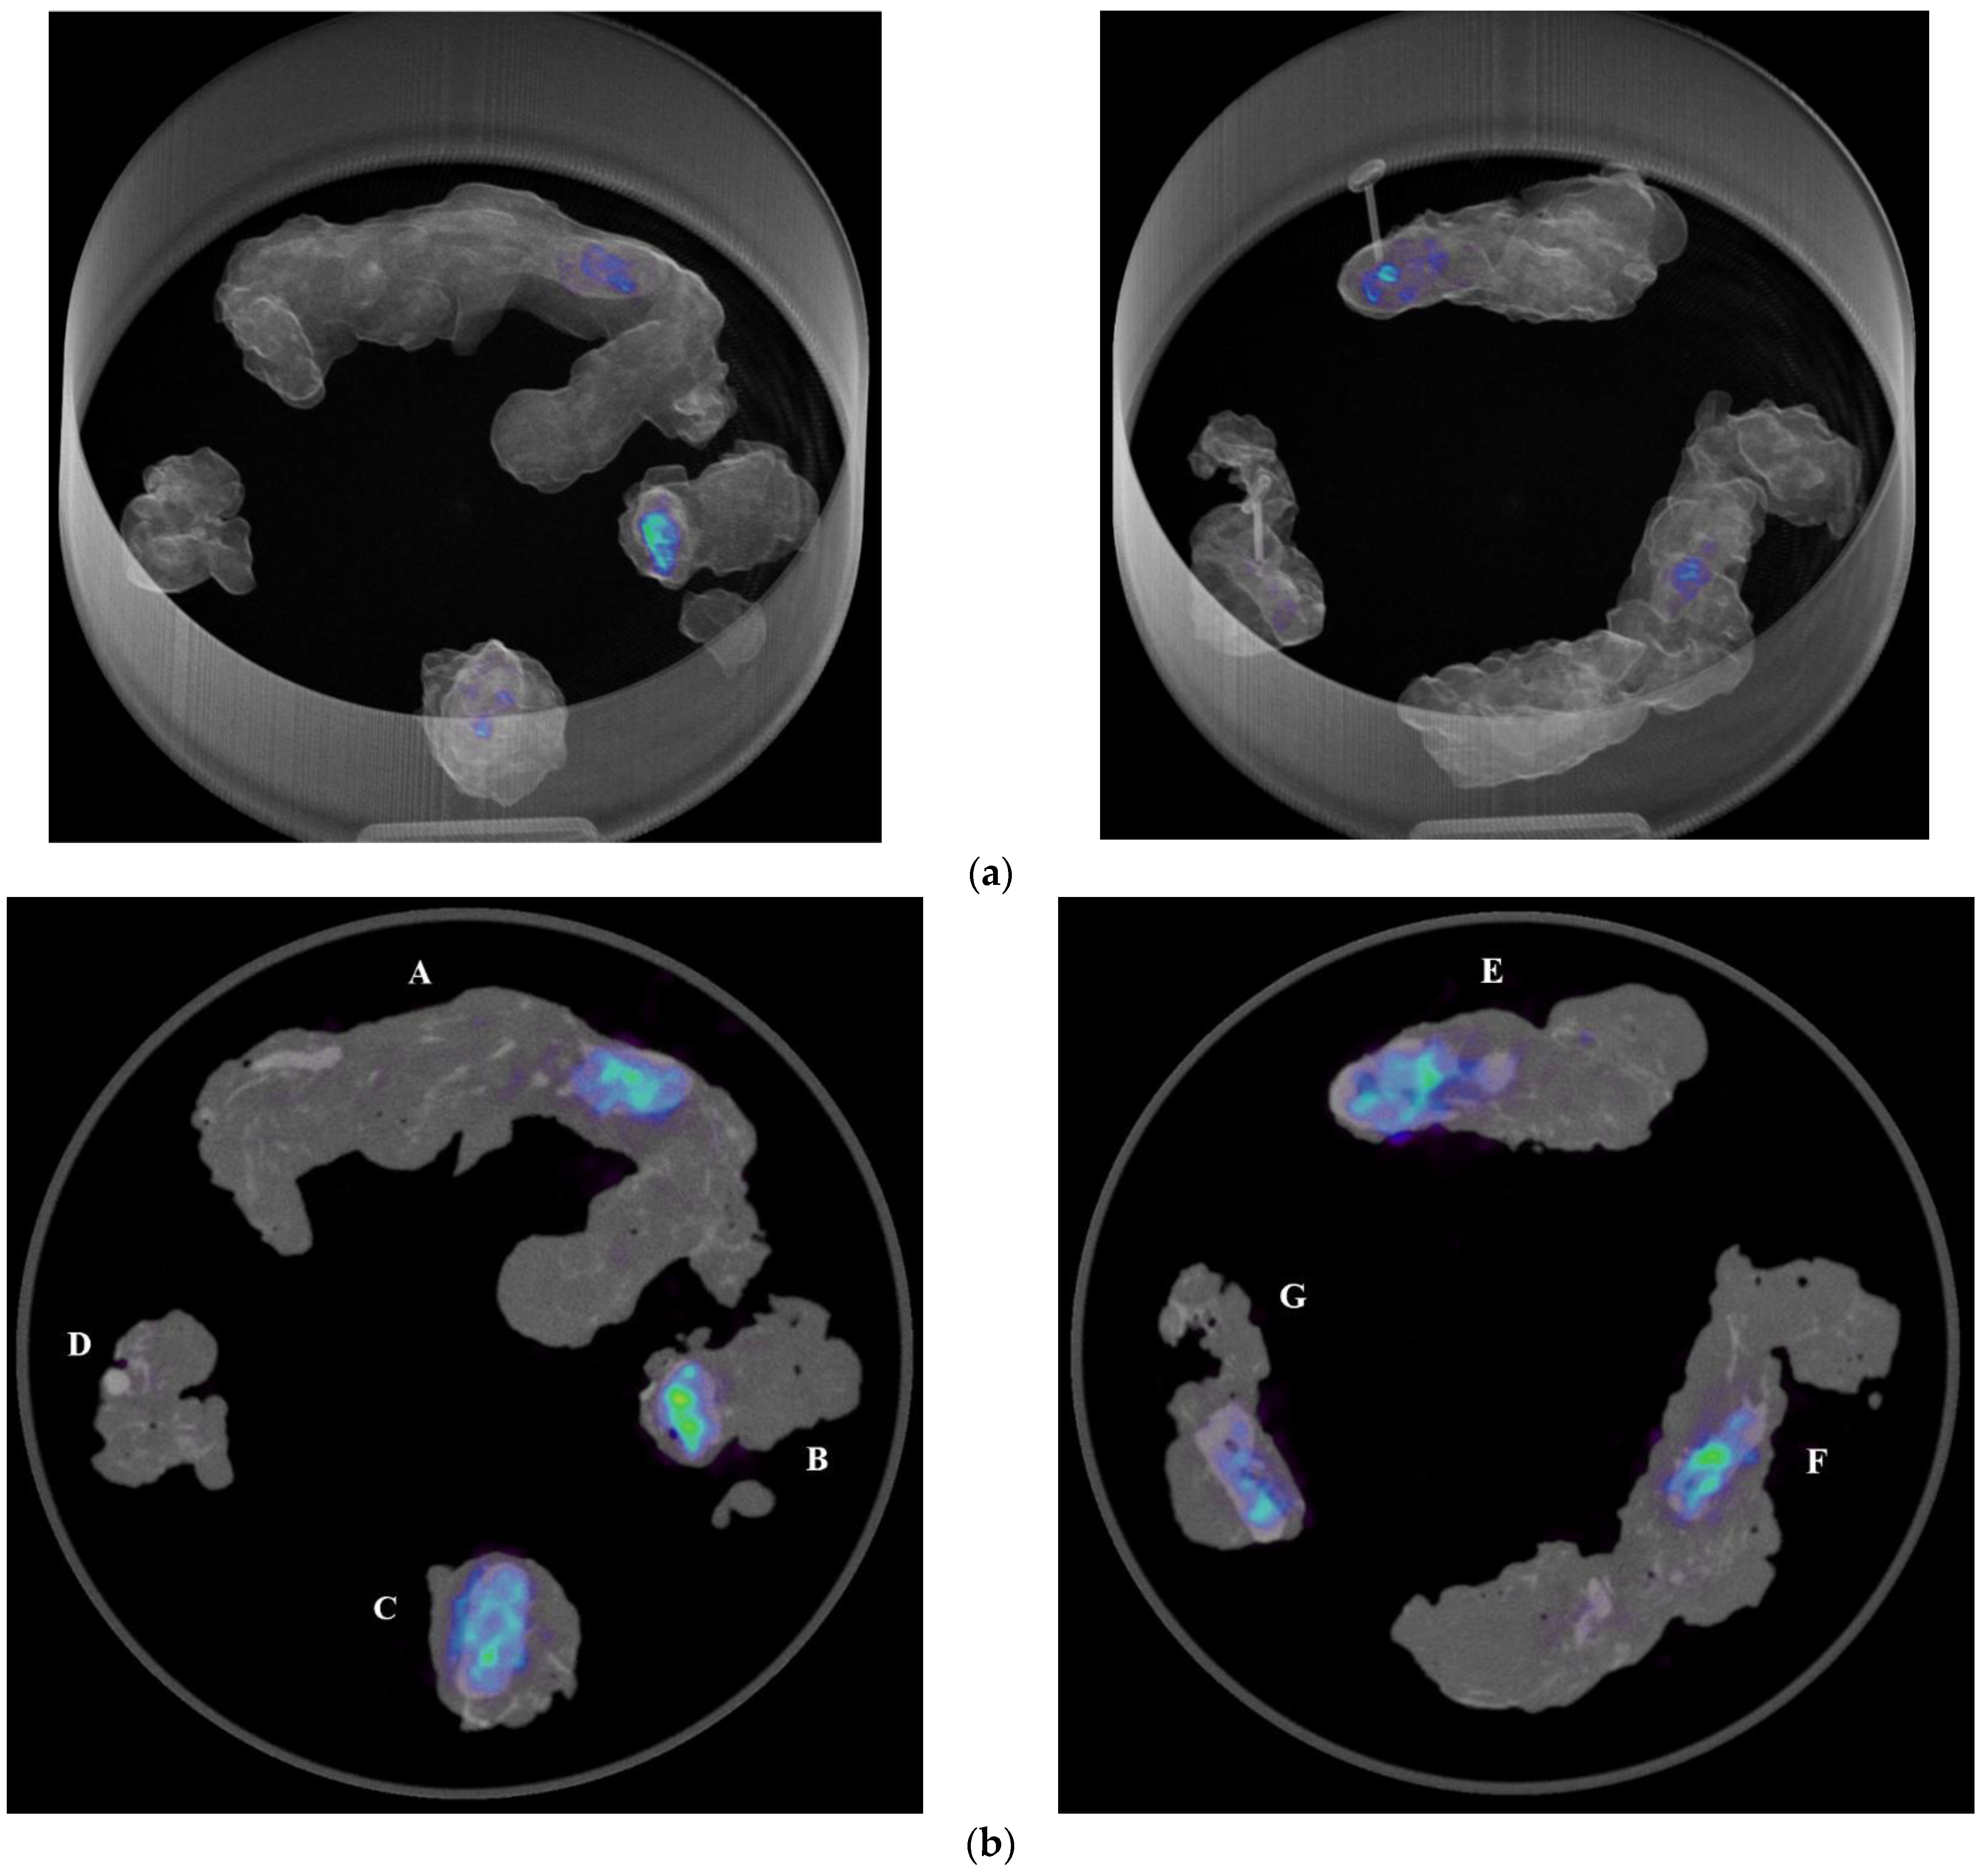

In the operating room, the acquisition of the specimens 68Ga-PSMA-11 PET/CT images with the intraoperative PET/CT scanner proved to be safe and feasible. The median time between radiotracer injection and specimen PET/CT imaging of the pelvic lymph nodes was 125 min. On average, the time required to complete the scanning process of a specimen case was 12 min. Figure 1a,b show the volume rendering of the PET/CT acquisitions, as well as two sample axial slices denoting mild tracer uptake in nodal structures.

Figure 1. (a) Volumetric rendering and axial view (b) of 68Ga-PSMA-11 PET/CT specimen images of the pelvic lymph nodes of a high-risk prostate cancer patient undergoing robot-assisted radical prostatectomy (RARP) and pelvic lymph node dissection (PLND). A, B: left obturator, C: left proximal external iliac, D: left distal external iliac, E: right distal external iliac, F: right obturator, G: right proximal external iliac.